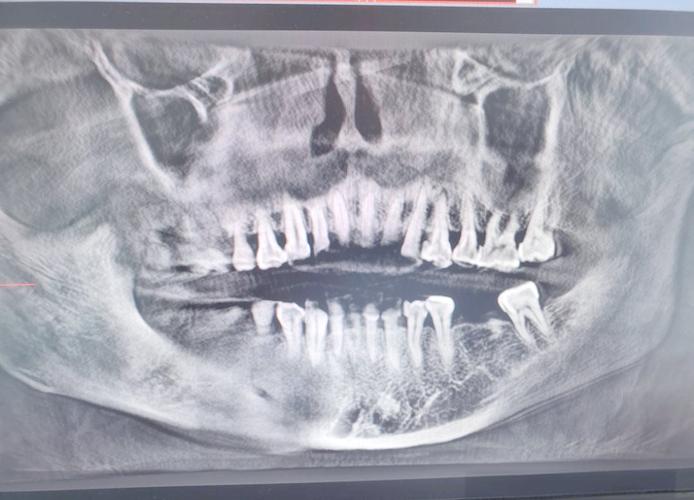

(图片来源网络,侵删)- 种植牙前:医生必须精确知道你要种牙的地方骨头够不够、够不够硬,离神经和上颌窦有多远,否则手术风险极高,CT是必不可少的。

(图片来源网络,侵删)